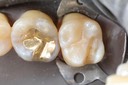

Alan Chinn #2 prep